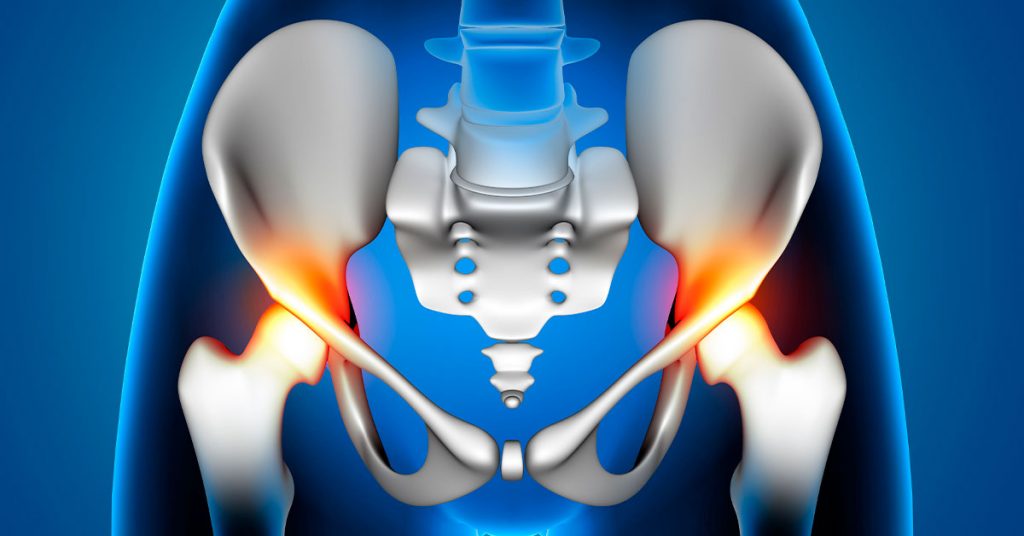

Ao todo, a fila declarada pelos estados é de 8.348 pacientes pacientes à espera de seis tipos diferentes de artroplastia de quadril. No procedimento, a articulação danificada é substituída por uma prótese de metal que adere ao osso e é recoberta por estruturas especiais de cerâmica ou polietileno.

De acordo com o ortopedista Jorge dos Santos Silva, diretor do serviço de emergência do Instituto de Ortopedia e Traumatologia do Hospital das Clínicas, o grande problema da artrose de quadril é a dor incapacitante.

“Prejudica a qualidade de vida do paciente, que convive com dor diariamente. Ele não consegue colocar uma calça, uma meia, amarrar um sapato. É um problema para quem precisa trabalhar, para quem quer fazer atividade física também.”

Silva lembra que a condição deve aumentar nos próximos anos em razão do envelhecimento populacional e prejudica ainda mais pacientes com doenças sistêmicas, como diabetes e obesidade.

Segundo ortopedista, há toda uma progressão de tratamentos até chegar na indicação cirúrgica, como fisioterapia e aplicação de ácido hialurônico no quadril.São tratamentos paliativos, que conseguem minimiza a dor por um tempo, mas só a artroplastia é considerada resolutiva. O presidente Lula, por exemplo, já passou por essas etapas.